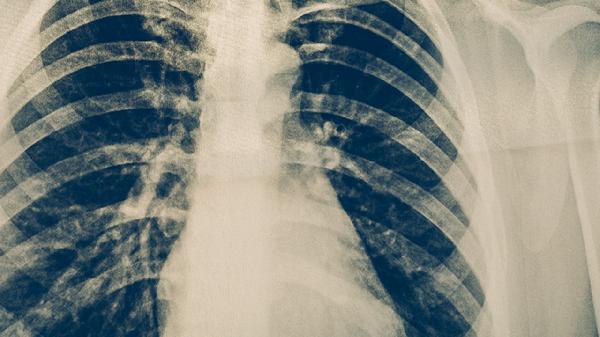

艾滋病患者、长期使用免疫抑制剂者、糖尿病患者等群体因免疫系统功能受损,对结核分枝杆菌的抵抗力下降,易感染肺结核。肺结节风险也因免疫力低下而增加,可能由潜伏感染激活或新发感染导致。这类人群需定期进行胸部影像学筛查,并在医生指导下评估预防性抗结核治疗的必要性。

矿工、纺织工人、建筑从业者等长期接触二氧化硅粉尘、石棉或工业废气的人群,肺部易发生炎性反应和纤维化,形成肺结节。同时粉尘环境可能破坏呼吸道防御机制,增加结核杆菌感染概率。职业防护需注重佩戴口罩、改善通风条件,并每年进行低剂量CT检查。

慢性阻塞性肺疾病、支气管扩张患者因气道结构异常和黏液清除能力下降,更易滞留结核杆菌导致感染。肺结节可能源于反复感染引发的肉芽肿或局部瘢痕。此类患者出现咳嗽咳痰加重时应及时排查结核,同时控制原发病以减少并发症。

烟草中的焦油和化学物质会损伤支气管纤毛功能,削弱肺泡巨噬细胞吞噬能力,使吸烟者肺结核发病率较常人高2-3倍。吸烟也是孤立性肺结节的重要诱因,可能与炭末沉积或炎性假瘤形成有关。戒烟可显著降低风险,戒烟5年后肺部防御功能逐步恢复。